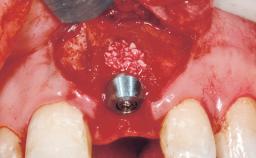

A 39-year-old male patient presented with a chief complaint of discomfort and gingival discoloration around his maxillary left central incisor. He was in good general health and was a non-smoker. His past dental history was significant because of the traumatic fracture of tooth 21 in a sporting accident at age 13. Initial dental treatment included endodontic therapy and a full-coverage restoration. The patient became symptomatic 5 years later, when structural failure of the tooth resulted in the dislodgment of the crown. Endodontic retreatment, apical surgery, and post-and-core restoration were performed.

Type of Implants One-Piece

Attachment One-Piece

Bone Augmentation Horizontal|Staged

Augmentation Materials Xenogenous|Membrane

Soft Tissue Grafting Simultaneous

Placement Protocol Early or late implant placement